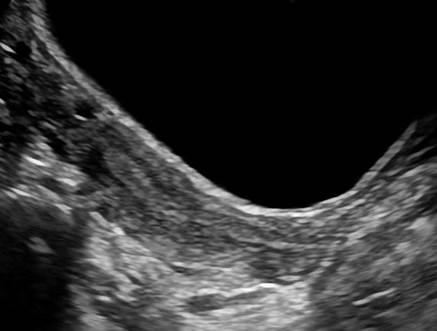

Dị dạng tử cung

Dị dạng tử cung - Ảnh 3

» Thông tin: Nữ giới – 14 tuổi.

» Lâm sàng: Kiểm tra sức khỏe.

# Tử cung có vách ngăn (Septate uterus).